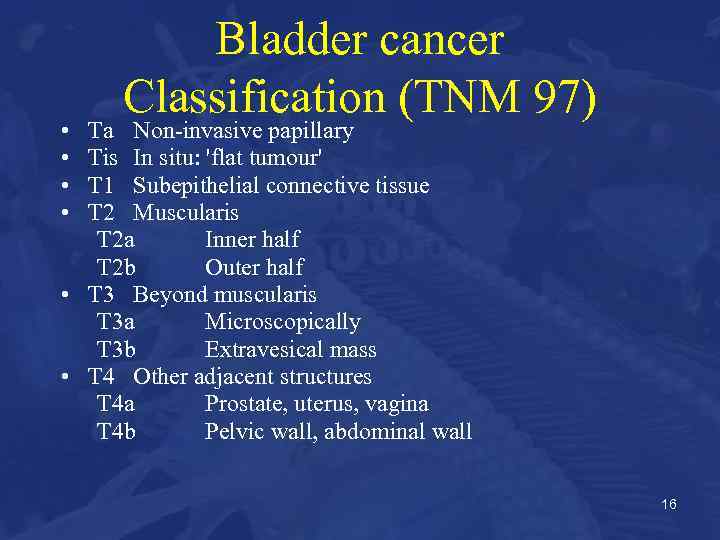

• • Bladder cancer Classification (TNM 97) Ta Non-invasive papillary Tis In situ: 'flat tumour' T 1 Subepithelial connective tissue T 2 Muscularis T 2 a Inner half T 2 b Outer half • T 3 Beyond muscularis T 3 a Microscopically T 3 b Extravesical mass • T 4 Other adjacent structures T 4 a Prostate, uterus, vagina T 4 b Pelvic wall, abdominal wall 16